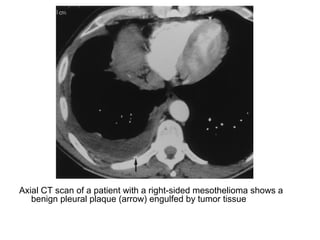

Axial CT scan of a patient with a right-sided mesothelioma shows a

benign pleural plaque (arrow) engulfed by tumor tissue